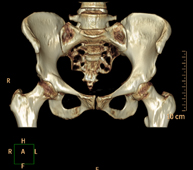

- Hip CT

Radiological examination based on an X-ray system and detectors that rotate around the patient, reconstructing the images by computer (multidetector computed tomography - MDCT) to study the bones, muscles and joints of the hips.